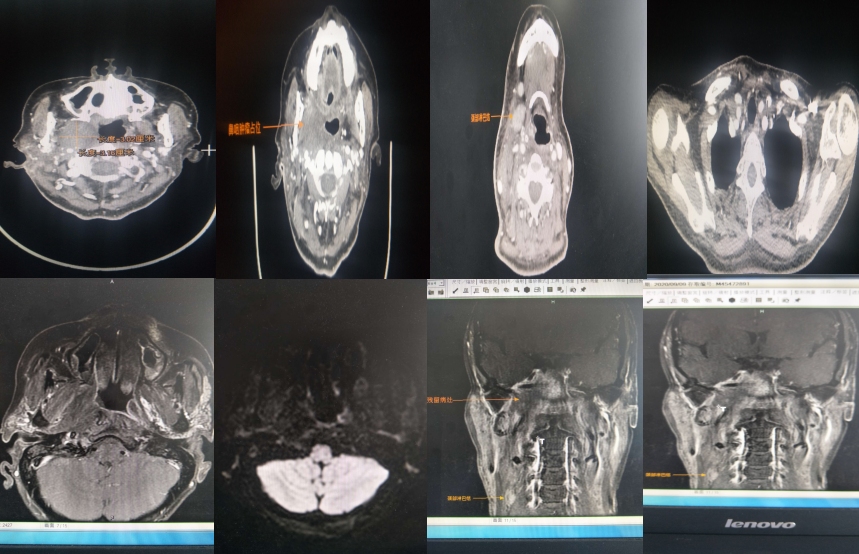

疗末复查CT及1月后复查核磁如下:

与治疗前相比,肿瘤明显缩小

影像学可见患者肿块明显缩小,颈部肿瘤有外观明显缩小。